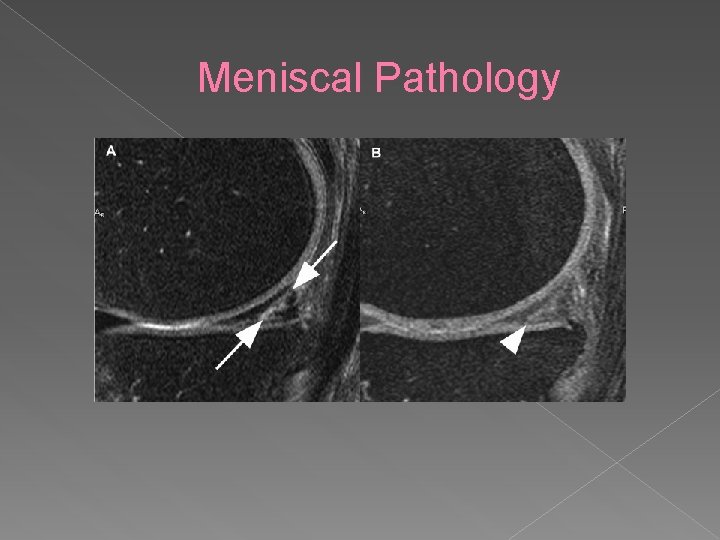

Meniscal Pathology